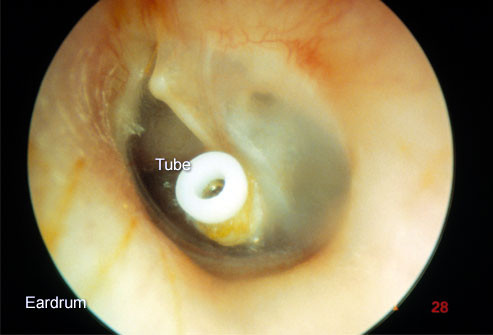

Viêm tai ứ dịch

![]() |

Tình trạng tích tụ dịch ở tai giữa (có hoặc không kèm theo đau) được gọi là viêm tai giữa ứ dịch. Bệnh thường diễn ra sau viêm tai cấp hoặc viêm đường hô hấp trên cấp.

Dịch thường tự hết trong vòng một hai tuần, tuy nhiên, nếu nó kéo dài hơn hoặc đặc lại giống như keo, nó có thể cản trở sức nghe của trẻ. Bác sĩ thường khuyên đặt ống tai để dẫn lưu dịch.